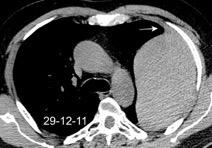

By-pass coronario 21-10-03

Marzo 2014: Perforación longitudinal distal secundaria a episodio de vómito (síndrome de Boerhaave). Derrame pleural izdo. que evoluciona a empiema.

Wang C-T et al. Tension hydropneumothorax in a Boerhaave syndrome patient: A case report . World J Emerg Med, 2021. Katabathina V et al. Nonvascular, nontraumatic mediastinal emergencies in adults:a comprehensive review of imaging findings. Radiographics. 2011.